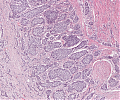

A63 Basaliom

Basaloide Tumorformationen mit palisadenartiger Begrenzung der Zellnester.

-

A63 Basaliom

Tumorinfiltration, ausgehend von der Epidermis

Basaliom_A63.png

Erkennbar sind Tumorzellnester mit pallisadenförmiger Anordnung der Tumorzellem am Rand